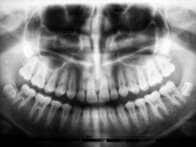

がん患者の歯のX線画像に映った「真っ黒な空洞」...歯科医が警告する「がんと歯」の意外な関係とは?